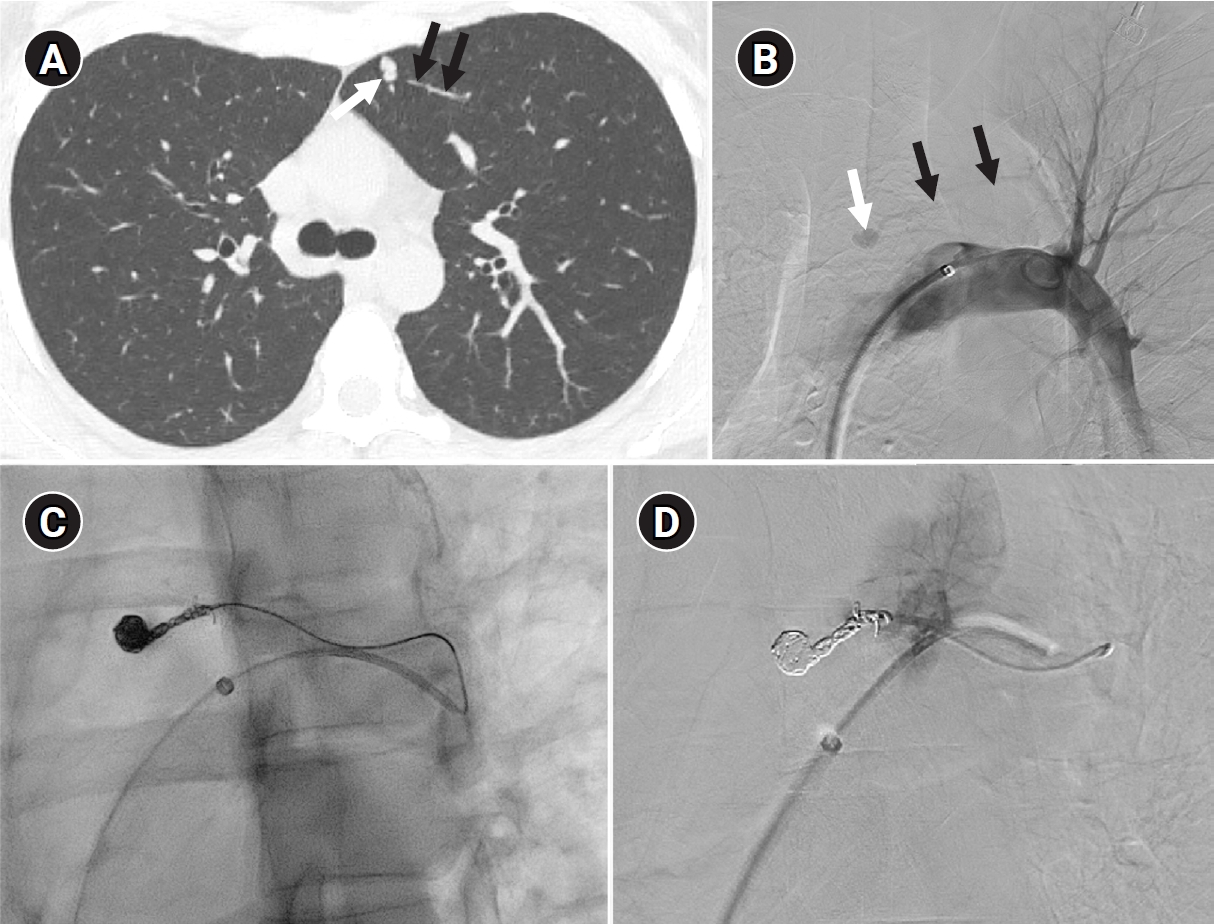

Fig. 2.

Embolization of a 1.5-mm feeding artery associated with an arteriovenous malformation in the left upper lobe of a 36-year-old female patient. (A) On the computed tomography (CT), a slender 1.5 mm feeding artery to the left upper lobe (black arrows) and a dilated venous sac (white arrow) are visible. (B) On angiography, the same finding as on the CT is observed (black arrows and white arrow), (C, D) A scene of coil embolization (C) and a post-embolization angiography image (D). In panel (D), the tri-axial system was utilized, including a 6-Fr Shuttle guiding catheter, a 5-Fr angled catheter, and a 1.9-Fr microcatheter, to access the feeding artery. Coil embolization was performed using Concerto 3D and Helix coils.

Fig. 2. Embolization of a 1.5-mm feeding artery associated with an arteriovenous malformation in the left upper lobe of a 36-year-old female patient. (A) On the computed tomography (CT), a slender 1.5 mm feeding artery to the left upper lobe (black arrows) and a dilated venous sac (white arrow) are visible. (B) On angiography, the same finding as on the CT is observed (black arrows and white arrow), (C, D) A scene of coil embolization (C) and a post-embolization angiography image (D). In panel (D), the tri-axial system was utilized, including a 6-Fr Shuttle guiding catheter, a 5-Fr angled catheter, and a 1.9-Fr microcatheter, to access the feeding artery. Coil embolization was performed using Concerto 3D and Helix coils.

To prevent paradoxical embolism or life-threatening bleeding, all detected PAVMs should be treated in adult patients. Historically, a feeding artery diameter of ‘3 mm’ was considered the minimal diameter criterion for treatment of PAVMs [2]. However, with advances in embolic devices and catheter systems, less than 3 mm feeding arteries ≥2 mm can now be embolized (Fig. 2) [11]. Pregnancy is a special risk factor in patients with PAVM, especially in the second and third trimesters due to a decrease in peripheral vascular resistance and an increase in cardiac output by nearly 50% [12]. A recent study in 244 pregnant women with HHT showed major complications in 13%, all in patients who had not been screened or treated for PAVMs prior to pregnancy [13]. Thus, all women with HHT considering pregnancy should be screened for PAVM with computed tomography (CT) and eventually treated prior to conception.

Historically, detachable balloons were used as an embolization material; however, they are no longer utilized in current practice [18]. In the context of PAVM embolization, the use of coils, vascular plugs, or a combination of both is now standard practice [19-21]. Since the development of detachable coils, they have offered advantages over pushable coils, particularly in terms of repositioning during the procedure. They can even be fully retrieved and redeployed if necessary, enhancing procedural safety and control. It is crucial to prioritize minimizing the recanalization rate while ensuring the overall safety of the procedure when selecting the appropriate embolic materials and techniques. Feeding artery coil embolization was historically regarded as the standard approach, whereas venous sac embolization was discouraged because of the perceived risk of rupture [22]. However, with the introduction of newer venous sac embolization techniques, recent findings now indicate that tightly packing the venous sac with coils can achieve a higher success rate than the traditional feeding artery approach (Fig. 2) [22-25]. Additionally, vascular plugs, including micro-vascular plugs (Medtronic, Minneapolis, MN, USA) and Amplatzer vascular plugs (Abbott Vascular, Saint Paul, MN, USA) have also demonstrated a higher success rate compared to feeding artery coil embolization (Fig. 4) [26-28]. In the case of vascular plugs, the risk of device migration is relatively low. Moreover, an additional advantage is that the device can be repositioned if the sizing is not ideal or if it is not deployed in the exact desired location. This flexibility enhances the precision of the procedure (Fig. 5). In a recent European guideline, there is also a recommendation to consider vascular plug embolization as a first-line option whenever possible, rather than coil embolization [11]. Additionally, a recent meta-analysis recommended vascular plugs or venous sac coil embolization, noting that vascular plugs had a recanalization rate of 13.6% compared to 32.7% for coil-only embolization. Similarly, venous sac embolization showed a 3.8% recanalization rate, while feeding artery embolization had a rate of 24.3%. Additionally, a recent meta-analysis has recommended the use of vascular plug or venous sac coil embolization, as these techniques have demonstrated a lower persistence rate compared to other methods [21]. This shift is largely in response to the relatively high recanalization rate associated with feeding coil embolization. In the case of embolization using vascular plugs, the plug should be deployed at the most distal segment of the feeding artery just before the venous sac in order to preserve the normal pulmonary artery. Since the pulmonary artery contains less elastin and has a thinner wall compared to systemic arteries, it is more distensible [29]. Therefore, in the author's experience, oversizing by about 50% to 100% has been effective in reducing the recanalization rate. When performing venous sac coil embolization, it is important to use coils large enough to create a stable framing coil larger than the draining vein diameter, thereby preventing coil migration. After establishing this frame, the venous sac and the proximal feeding artery should be carefully packed to achieve complete occlusion.